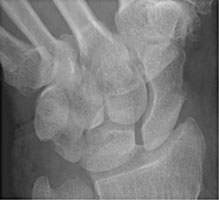

- Click on the image for a larger versionBPA radiograph of the wrist. This demonstrates a scaphoid waist fracture.